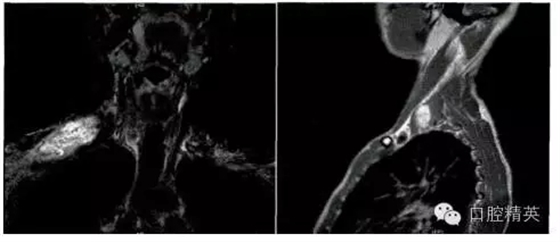

影像學(xué)檢查:頸部MRI(平掃+增強(qiáng))提示右肩部鎖骨上區(qū)皮下軟組織內(nèi)一巨大腫物,大小約6.1 cm×2.8 cm,其內(nèi)信號不均勻,T1W1為等信號,T2W2為混雜高信號,考慮神經(jīng)源性腫瘤,右側(cè)臂叢神經(jīng)可疑受累(圖1)。臨床初步診斷為“右頸神經(jīng)鞘瘤”。

圖1.頸部MRI示右鎖骨上區(qū)皮下軟組織內(nèi)一巨大腫物